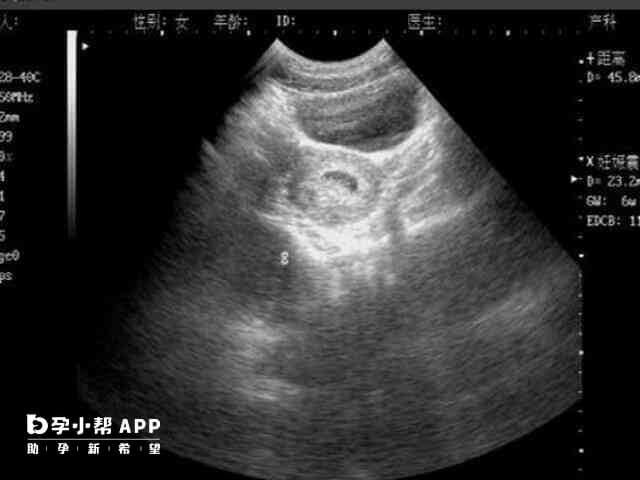

孕三个月做nt检查的时候,若是面积较小的宫腔粘连带对于胎儿是没有什么影响的,但是其粘连带面积比较大的话,就会容易导致胎儿出现流产、早产、胎儿肢体被缠绕,甚至严重勒伤等不良情况的发生,所以孕三个月做nt有宫腔粘连带的女性一定要注意监测B超,定期观察,在孕4/5个月出现胎动之后,需要注意胎动是否正常,若是不正常就需要及时就医。nt有宫腔粘连带对胎儿的影响宫腔粘连带实际上属于宫腔粘连的范围,是指宫腔内膜...